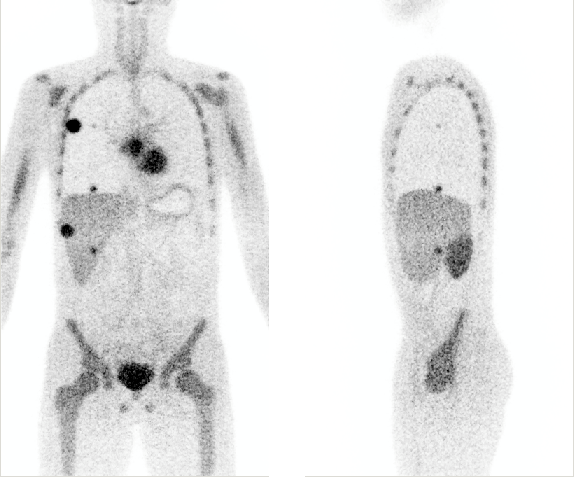

QETIR, which stands for Quantitative Emission Tomography Iterative Reconstruction is image reconstruction software for PET developed at Medisip. It utilizes listmode reconstruction as opposed to the more commonly used sinogram reconstruction. Implemented algorithms include (Time-of-Flight) MLEM, OSEM, MLTR, MLAA and MLAA+. Data from any scanner can be reconstructed if the scanner geometry is provided. Researchers interested in QETIR software can contact MEDISIP lab.